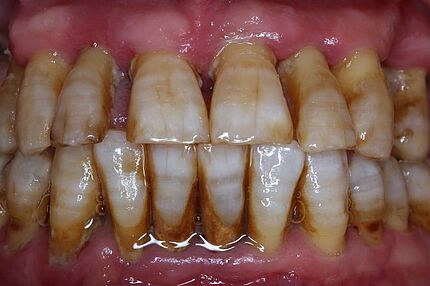

Ein 34-jähriger Patient hatte die häusliche Mundhygiene ohne erkennbare Gründe fast vollkommen eingestellt. Die daraus resultierende desolate orale Gesamtsituation war mit seinem äußeren Erscheinungsbild und seinem sozialen Status nicht vereinbar. Aufgrund dieser Widersprüche erfolgte eine intensive Abwägung der Therapieoptionen.

Zeitschrift: ZM – Zahnärztliche Mitteilungen

Ausgabe: 21/2019, Seiten 46 – 50

Freigabe zur Veröffentlichung erteilt durch den Deutschen Ärzteverlag

Autoren: PD Dr. Michael Korsch, M.A., Dr. Abdel-Karim Mamar